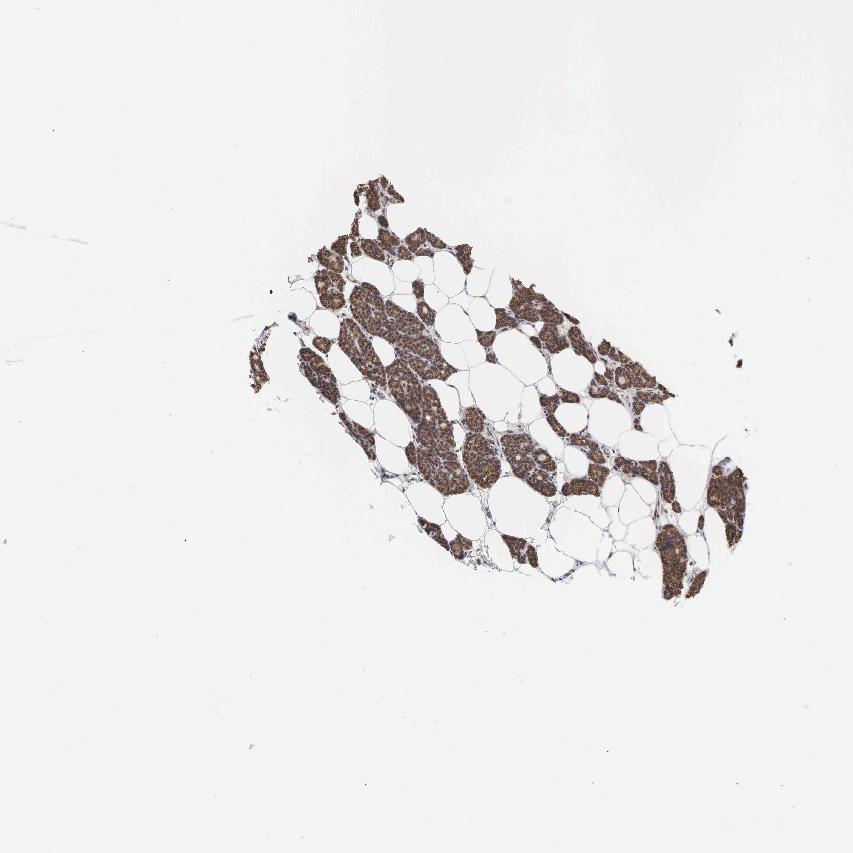

TISSUE PRIMARY DATA PARATHYROID GLAND Show tissue menu

PARATHYROID GLAND - Antibody stainingi

Antibody staining in the annotated cell types in the current human tissue is reported as not detected, low, medium, or high, based on conventional immunohistochemistry profiling in selected tissues. This score is based on the combination of the staining intensity and fraction of stained cells.

Each image is clickable and will lead to virtual microscopy that enables deeper exploration of all samples and also displays staining intensity scores, fraction scores and subcellular localization as well as patient and tissue information for each sample.

Antibody HPA000164Antibody HPA000165

Glandular cells MediumHigh